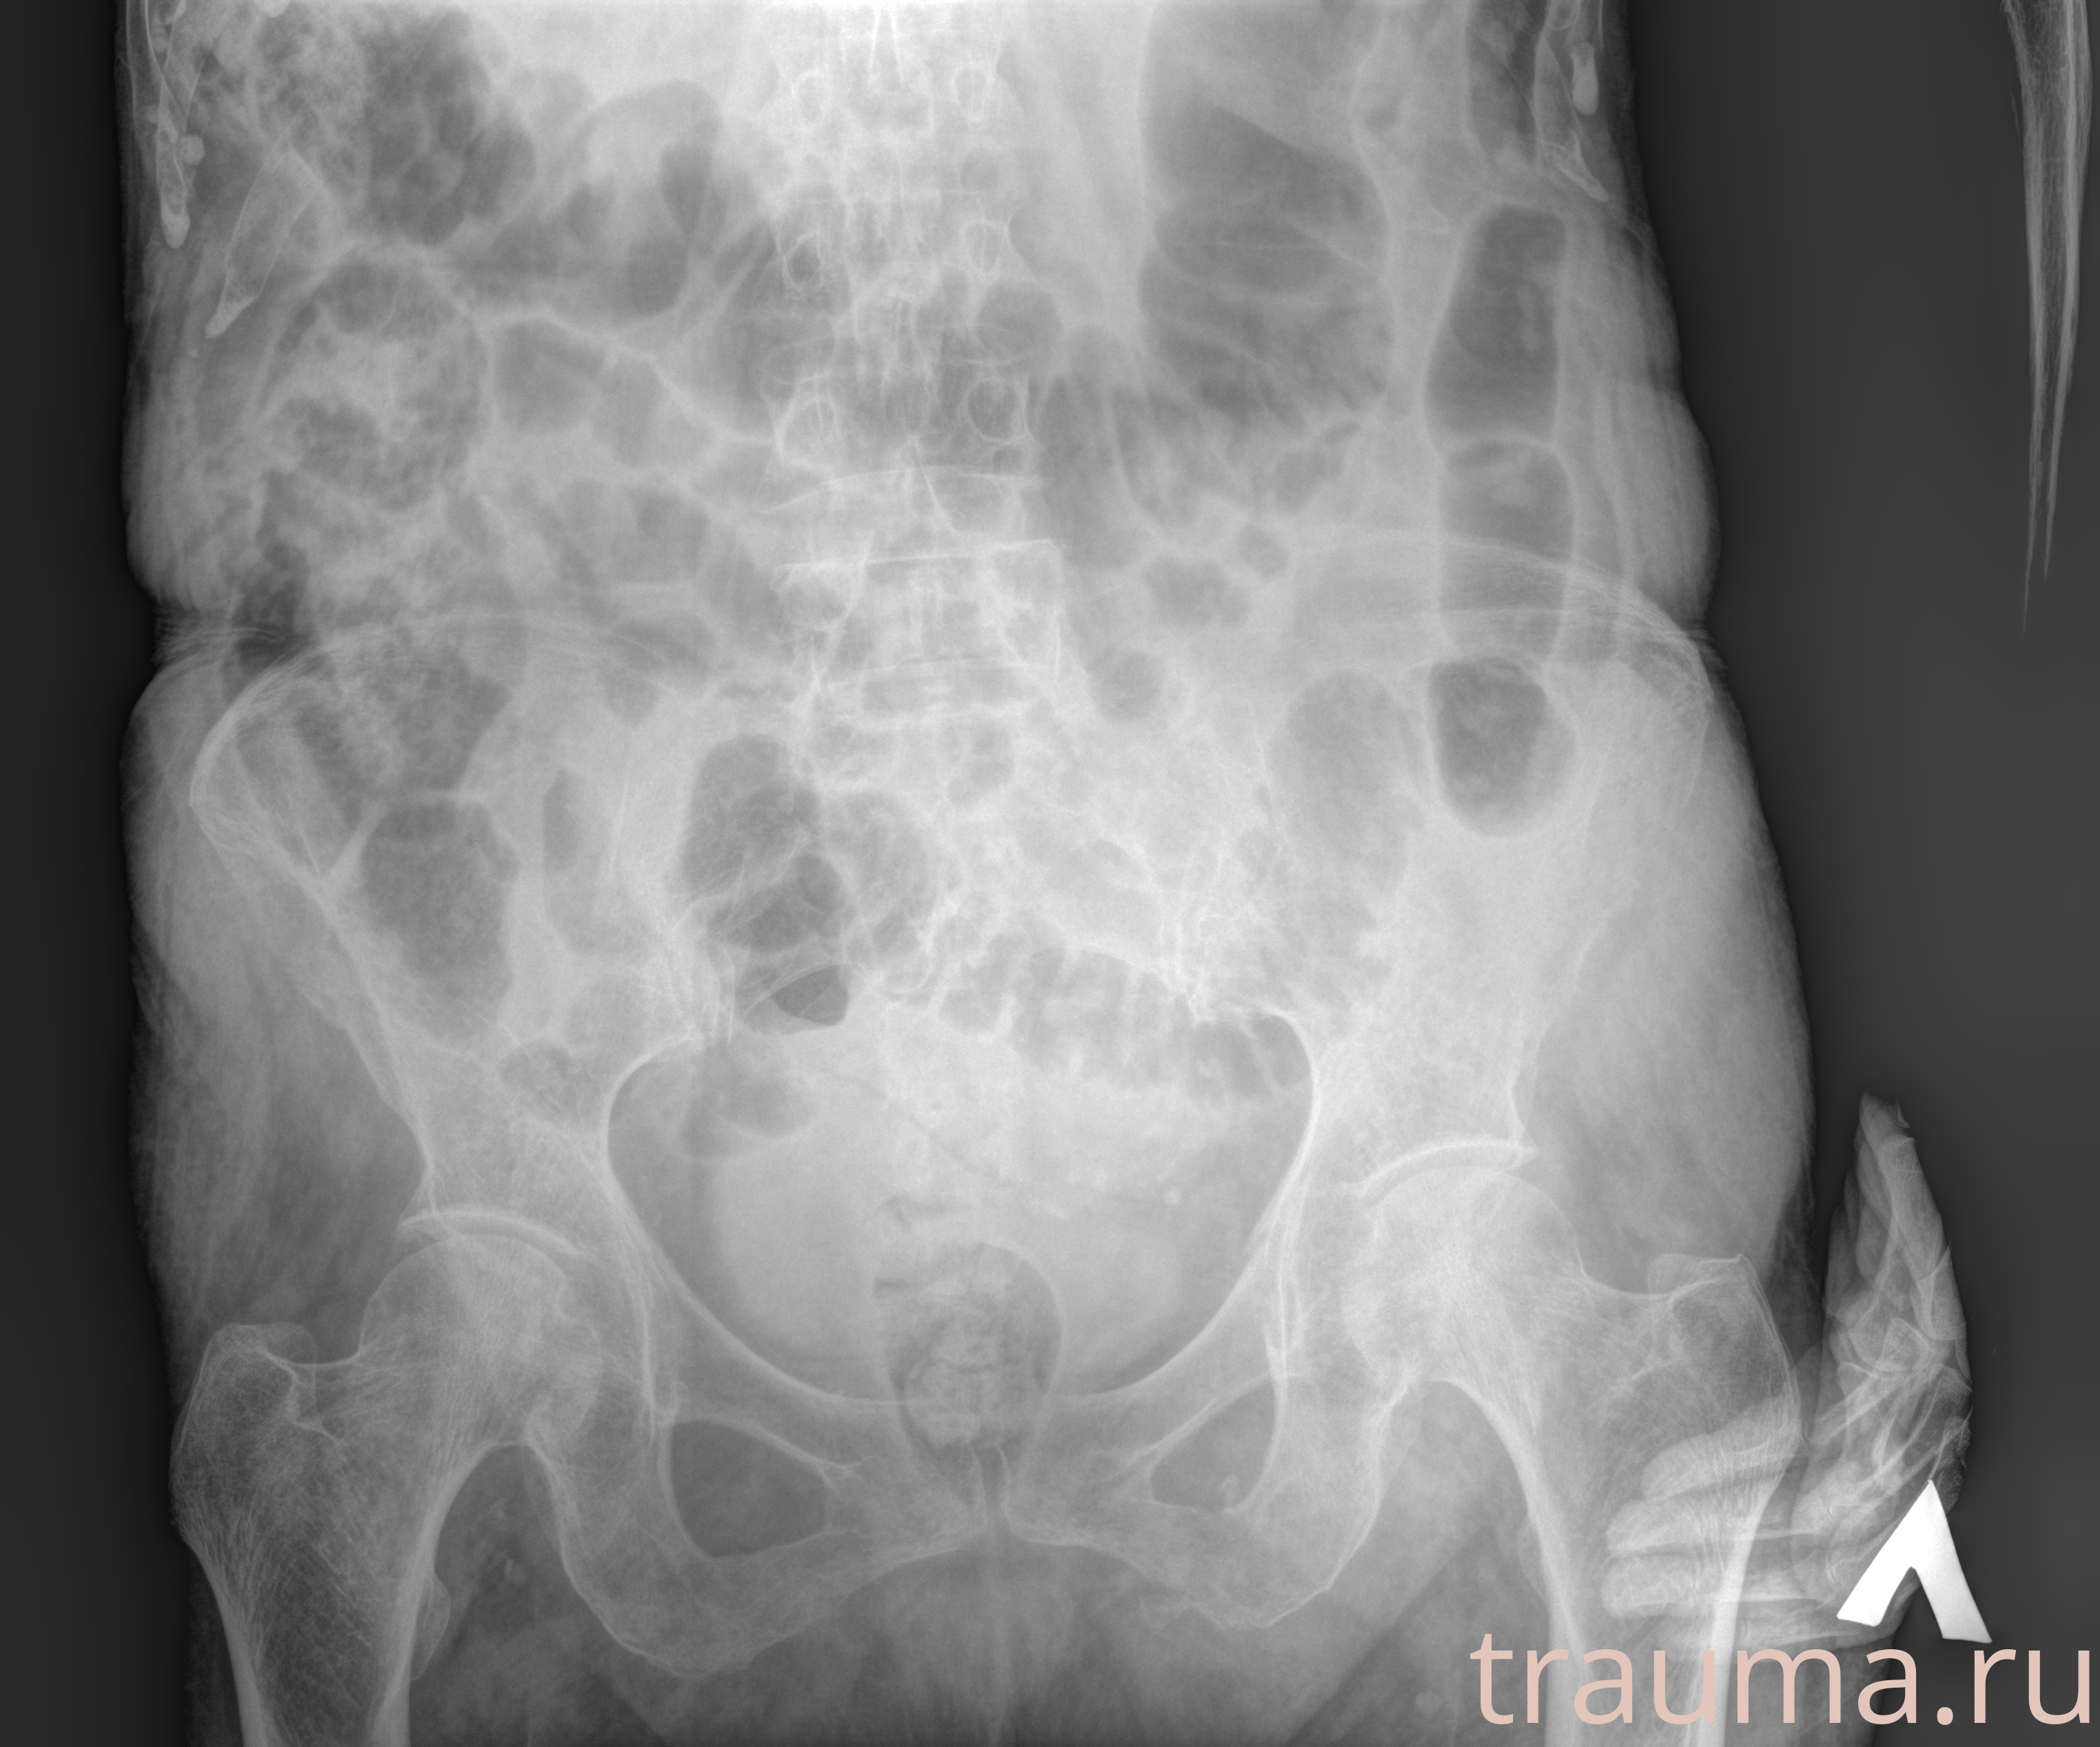

Рентгенограммы

Рентген на дому: по вашему адресу приезжает врач-рентгенолог, травматолог-ортопед с мобильным рентгеновским аппаратом, проводит диагностику травмы или заболевания, делает необходимые рентгенограммы, дает рекомендации по дальнейшему лечению. Получить качественные снимки в домашних условиях возможно благодаря уникальной методике, разработанной МосРентген Центром для института  Склифосовского